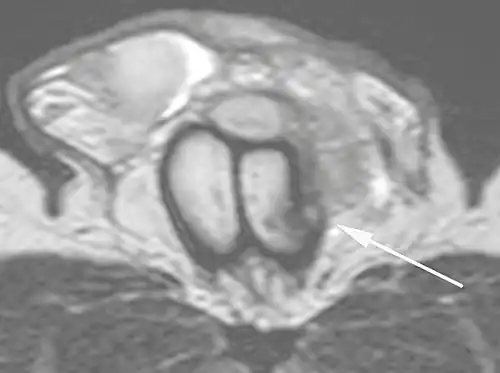

In the ultrasound examination, a lesion of the tunica albuginea presents as an interruption in (loss of continuity of) the echoic line representing it (Figure 4). Small, moderate, or broad hematomas demonstrate the extent of that discontinuity. Intracavernous hematomas, sometimes without the presence of a tunica albuginea fracture, can be observed when there is a lesion of the smooth muscle of the trabeculae surrounding the sinusoid spaces or the subtunical venular plexus.[2]

Figure 4 A: Ultrasound of the penis, right lateral view. Longitudinal section showing rupture of the tunica albuginea with an adjacent 1.92 cm hematoma (between calipers), due to trauma.[2] -

B: Axial T2-weighted turbo spin-echo magnetic resonance imaging scan showing left-sided discontinuity of the tunica albuginea (arrow), secondary to fracture.[2]